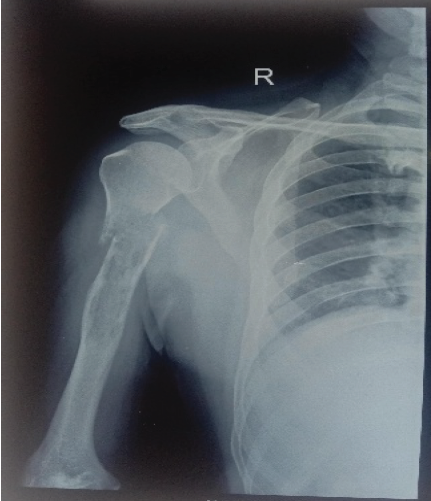

Investigation

Radiograph of right arm shows pathological fracture of right shaft of humerus (Fig. 7).

Figure 7 : Plain radiograph of the right arm showing pathological fracture of the right shaft of humerus (55-year-old male with multiple myeloma for 3 years). The lytic lesion at the humeral shaft demonstrates tumor involvement characteristic of multiple myeloma-related pathological fracture.

Intervention

Patient was managed with closed reduction and internal fixation using IM humerus nailing (Fig. 8) along with biopsy.

Figure 8 : Postoperative radiograph of the right humerus following closed reduction and internal fixation using intramedullary humerus nailing. The locked intramedullary nail secures the pathological fracture, enabling functional recovery and pain relief. The minimally invasive approach minimizes soft tissue trauma and operative morbidity.